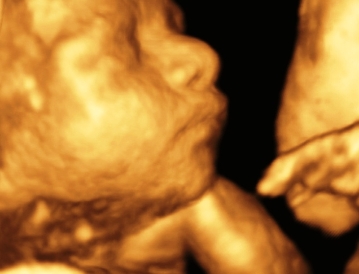

Manos